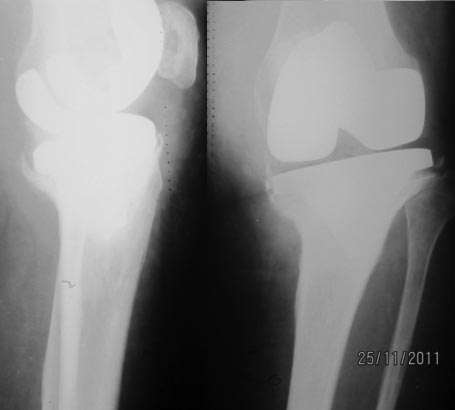

Xray1. Рентгенограмма коленного сустава 20.04.07. Спустя 1,5 года

после тотальной артропластики.Xray2. Рентгенограмма коленного сустава после

имплантации спейсеров. Спустя 5 лет и 9 месяцев после операции тотальной

артропластики.Заранее благодарим!